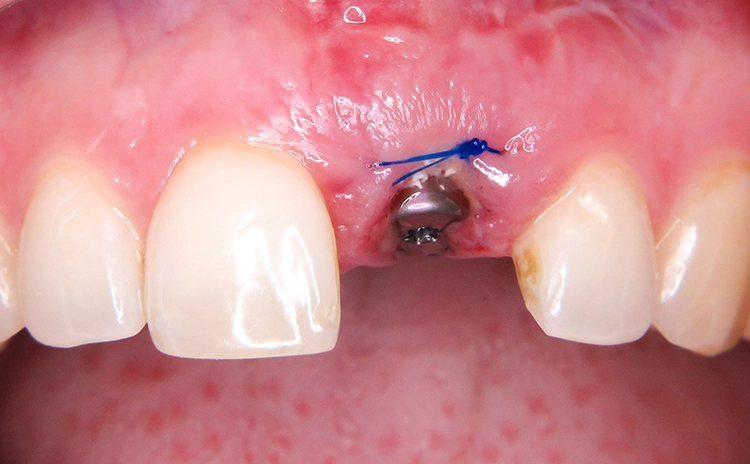

Chirurgischer Eingriff: Extraktion und Insertion

Unter Lokalanästhesie wurde der beherdete Zahn 21 extrahiert und hierbei auf die maximale Schonung der vestibulären Lamelle geachtet. Die Entzündung konnte rückstandslos entfernt werden. Die Sondierung ergab eine intakte faziale Knochenlamelle (Abb. 6). Die frische Extraktionsalveole wurde als Implantatbett aufbereitet und das Implantat (BLX ø 4 mm, 14 mm) entsprechend der Planung dreidimensional im palatinalen Bereich der Alveole inseriert [3,6] (Abb. 7 und 8).

Augmentation

Der Spalt zwischen dem Implantat regio 21 und der vestibulären Alveolenwand (Jumping Distanz) wurde mit Knochenersatzmaterial (cerabone, Botiss) gefüllt (Abb. 13 und 14). Ziel einer Augmentation im Bereich der vestibulären Alveolenwand ist eine verbesserte Regenerationsfähigkeit der Hart- und Weichgewebe [15]. Um einen Kollaps der Weichgewebe zu verhindern, sollte die Alveole innerhalb kürzester Zeit versorgt werden.

Der Resorption der bukkalen Lamelle soll durch die Augmentation bestmöglich entgegengewirkt und die Knochenneubildung unterstützt werden. Erfahrungsgemäß führt das Füllen des Gaps in vielen Fällen zu einem besseren Ergebnis. Aufwendige Folgeaugmentationen lassen sich oft vermeiden. Verwendet wurde in diesem Fall ein Knochenersatzmaterial [4]. Nach dessen Einbringen und dem Aufsetzen der Abdeckschraube wurde die Situation mit einer Matratzennaht verschlossen (Abb. 15).